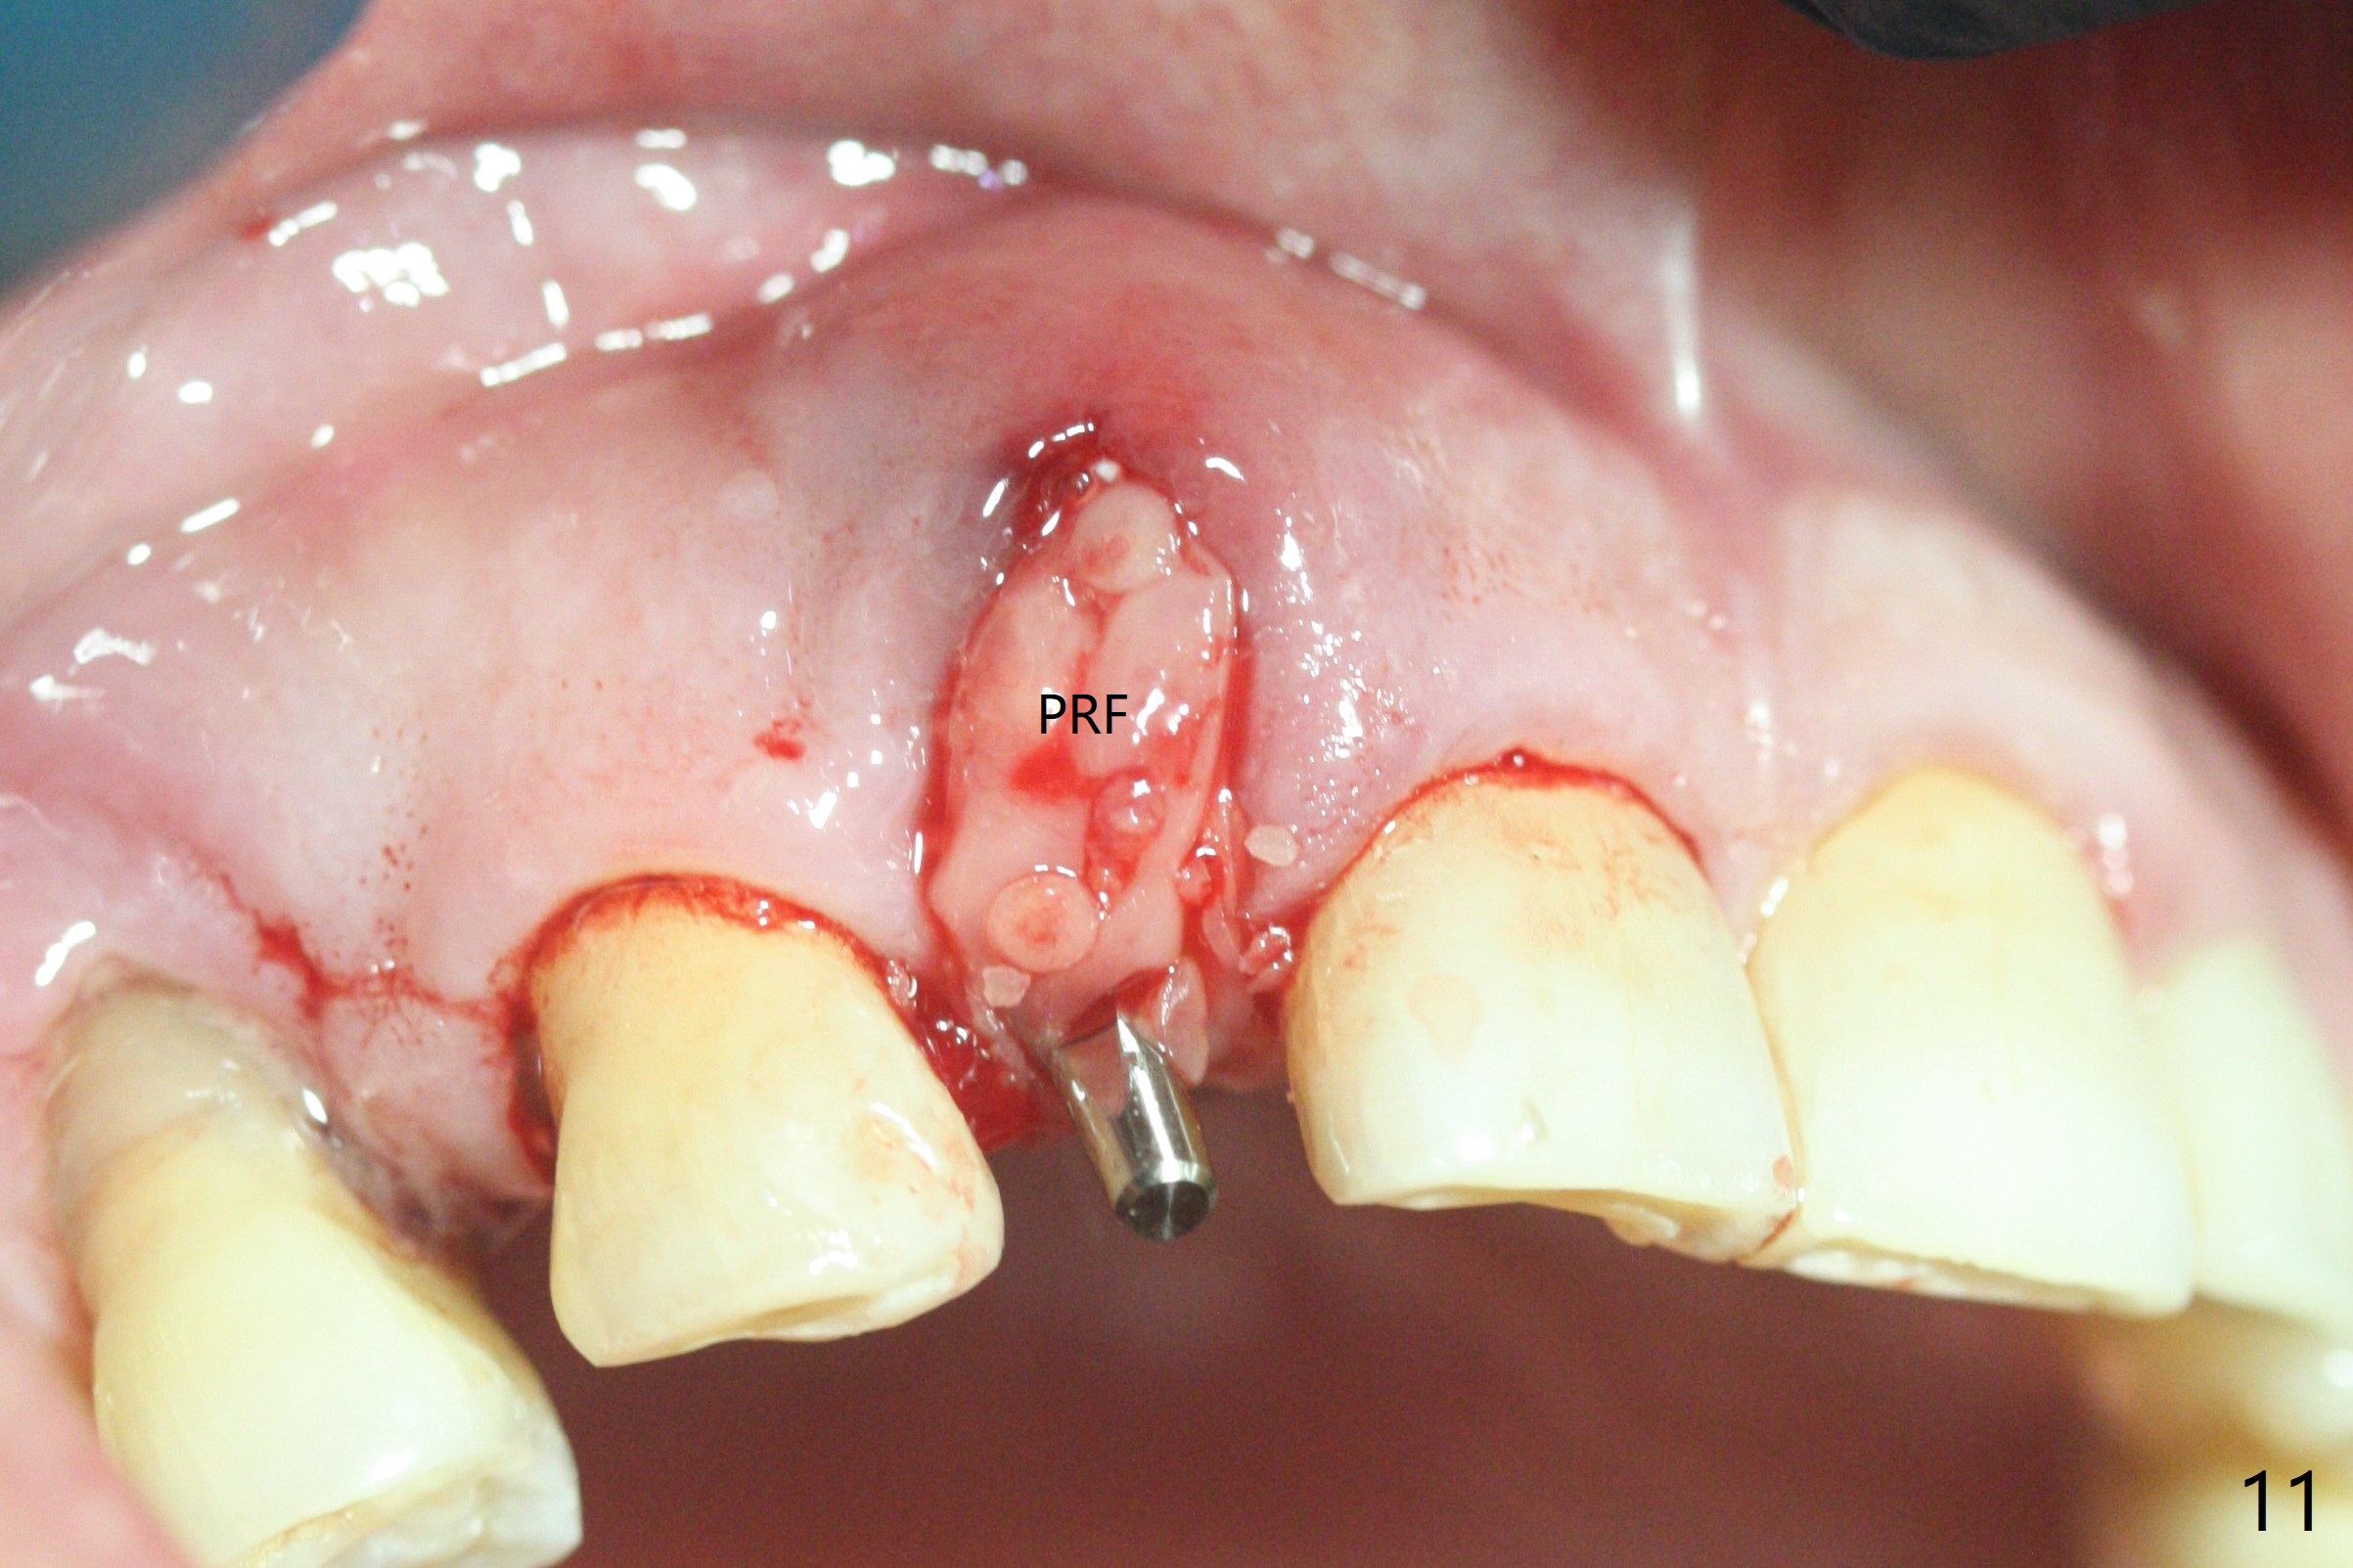

68岁男士右上2严重骨质吸收,颊侧骨板缺失,术前牙龈退缩也十分明显(图一,二),术中对脆弱牙龈缘(图三:*)不应施加任何压力或者牵拉,更不能切开,保持最佳血供。按照术前设计,在牙槽窝腭侧钻洞(图四),植入2.5x15毫米一段式植体(扭力>35Ncm),基台特长(牙龈厚,图五)),基台位于合适修复位置(图六),4-5毫米螺纹颊侧暴露(图七:*)。植骨(图八(CT冠状切面(拔牙后:黑色)):箭头)前,将PRF膜(白线)一头(a)插入牙槽窝颊侧,另外一头(图八,九:b)放置颊侧牙龈颊侧。然后填入粘性骨粉(图九:S;图十四:*),将b头PRF膜往下翻,它末端事先冲一个洞(punch a hole using sterilized rubber dam punch),插入基台(图十(粉红色),十一),这样PRF膜不移位,牢靠地固定骨粉(图十(红圆圈),图十四:*),最后使用树脂敷料覆盖伤口(图十二,十三:A),同样需要基台(箭头,也就是一段式植体)固定,也就是没有即刻植体,就没有骨粉固位。术后两个月伤口缩小,肉芽组织生长(图十五)。撤除树脂敷料后,制作临时牙冠,半个月后唇侧植体有些暴露(图十六),嘱咐强化口腔卫生。